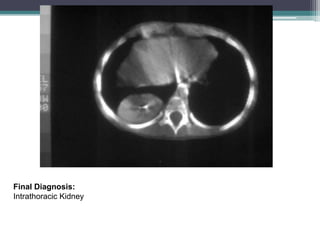

PA and lateral chest films show a soft

tissue mass in the right posterior

costophrenic sulcus.

Final Diagnosis:

Intrathoracic Kidney